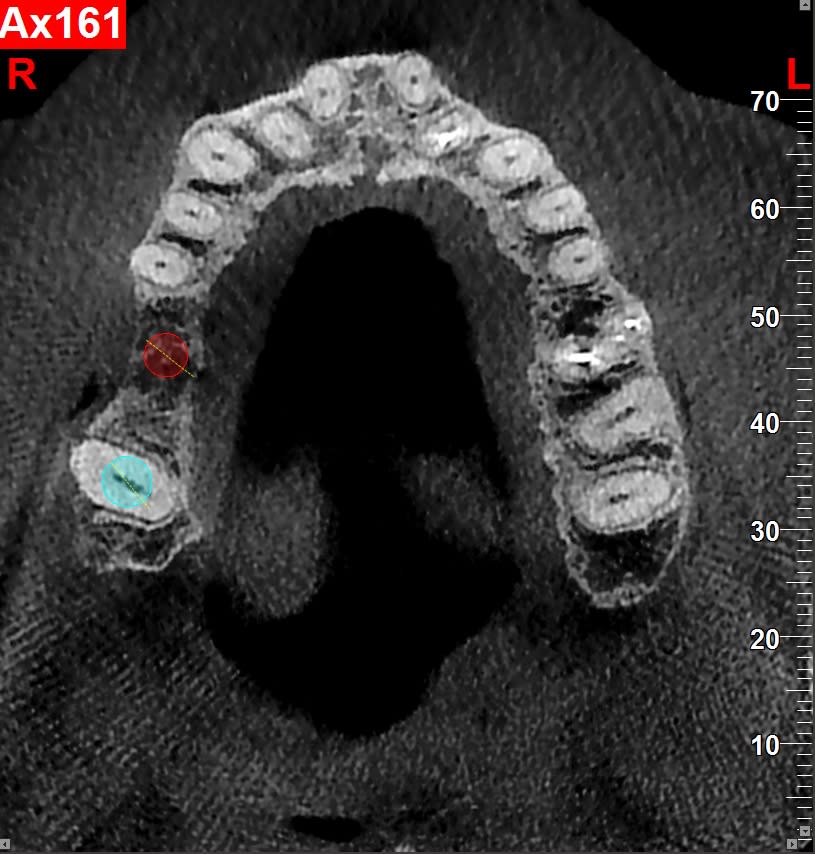

Par contre est ce que la mésialisation de la 18 est possible même si le sinus plonge au niveau de l'édentement de la 17 ancien et qu'il n'y a pas d'os en mésial ? Ça va se remanier tout seul ?

Si on doit placer une vis de traction, où la mettre ? à la place de la 16? Ou peut-on se servir de l'implant en 16 pour tracter la 18 ?

oui, un implant peut servir d'ancrage pour tracter la 18 (après son ostéointégration bien sûr...;-)

Implant en 16, on attend trois mois, provisoir et l on tracte la 18 avec bague sur 17 18.

Juste pour info il n'y a pas de contre indication particulière à bouger une dent qui est contre le sinus. Dans certain cas ça peut ralentir le mouvement mais c'est plus ou moins tout. Clairement pas un soucie si il y a un implant.

Extraction de 16 et 26, 17 et 27 étant clairement contre le sinus.